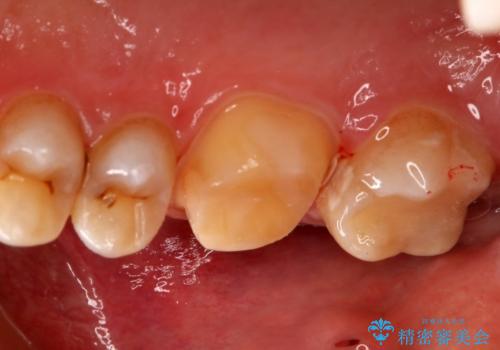

- 右上下6番の銀歯のやり変えを希望された患者様です。

切削量・形態を考慮し、上はセラミッククラウン、下はセラミックインレーでの治療を選択しました。

上はう蝕が歯頚部まで達していたのでクラウンでの治療を選択しました。

銀歯直下もう蝕が進行していたので全て除去した上でCRにて裏層しています。

下はクラウンほど切削量が多くないと判断し、インレーでの治療を選択しました。